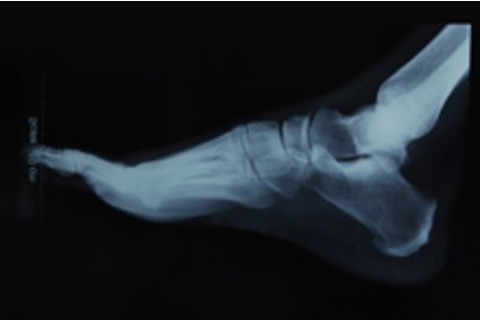

尽管近期的医学取得了惊人的进展,但仍然有很多简单的问题缺乏明确的解决方案。例如,我们仍然没有找到一种很好的方法来治疗关节顶部骨骼的骨折——骨骼修复过程中任何对齐错误,都会导致关节无法使用,更不用说可怕的关节炎了。犹他大学的一组生物工程师提出一个巧妙的想法:如果沙堡蠕虫能够产生足够坚固的天然胶水,以抵御潮间带海浪的冲击,将沙子家园粘合在一起,为什么不复制这种胶水,并将其用于骨折的膝盖呢?目前,这种所谓的蠕虫胶的原型第一代已经在牛骨碎片(来自食品,意味着牛已经死亡)上进行了测试,其性能相当于商业强力胶的37%。研究结果将在下周的《

罗素·斯图尔特预计他们将在一年或两年内对活体动物进行胶水测试,并在未来5到10年内对人类进行测试。虽然这种胶水无法修复你断裂的股骨,但它对骨折的膝盖、手腕、肘部和脚踝中的小骨碎片,以及面部和头骨都可能非常有用。最重要的是,这种胶水可以携带药物,这意味着它可以用来将止痛药、抗生素、抗炎药甚至干细胞输送到骨碎片粘合的部位。 试试看有没有一瓶白乳胶能做到这些。 相关内容:80Beats: 科学家们制造出一种基于壁虎脚掌模型的超强纳米科技胶 Disco: 自修复飞机在飞行中自行修复